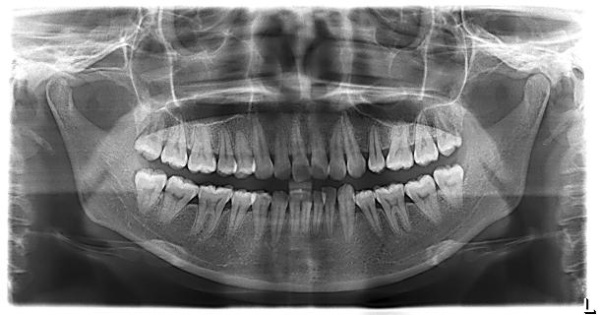

口腔全景片,顧名思義(yi) 就是可以把全口牙齒都展現出來的一種牙片,這是牙科比較常見的片子,一般就是這樣的:

拿到一張口腔全景片後,我們(men) 先要根據牙片上標誌的R和L字母來分辨左右,R代表的是口腔右側(ce) ,而L代表的就是口腔左側(ce) 。

除此之外,口腔全景片可以看到什麽(me) 東(dong) 西,一般來說,可以看到全口牙齒、牙周、牙槽骨情況、上下頜骨情況以及上頜竇、鼻腔等他們(men) 的位置、形態等。